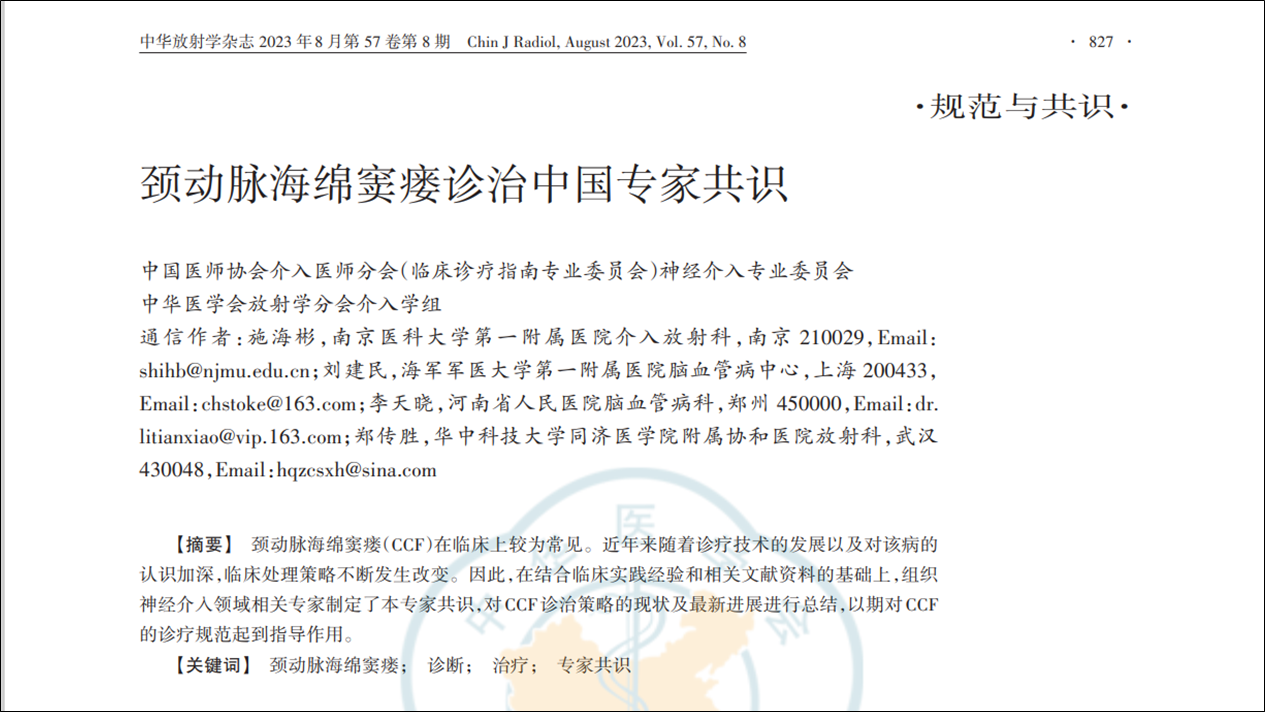

现病史:12小时前无明显诱因突发出现右侧肢体无力,伴言语不能,伴呕吐胃内容物3次,无人事不省,无肢体抽搐,无发热等。就诊当地医院,急查头颅CT示:“颅内出血”,予对症处理后转诊我院。我院急诊查头颅CTA示:“左侧基底节区及左侧额颞叶血肿伴大脑镰下疝、颞叶钩回疝及海马旁回疝可能,左侧颈内动脉C4段所见,考虑多发动脉瘤伴血管畸形,建议DSA检查”。

影像资料:CT、CTA

1.左侧基底节区及左侧额颞叶血肿 2.左侧颈内动脉C4段多发动脉瘤 3.左侧额颞叶血管动静脉畸形

1. 左侧基底节区及左侧额颞叶血肿

精确诊断:左侧颈内C4段动脉瘤破裂至大脑中浅静脉致左侧基底节区及左侧额颞叶静脉性梗死并出血转化。